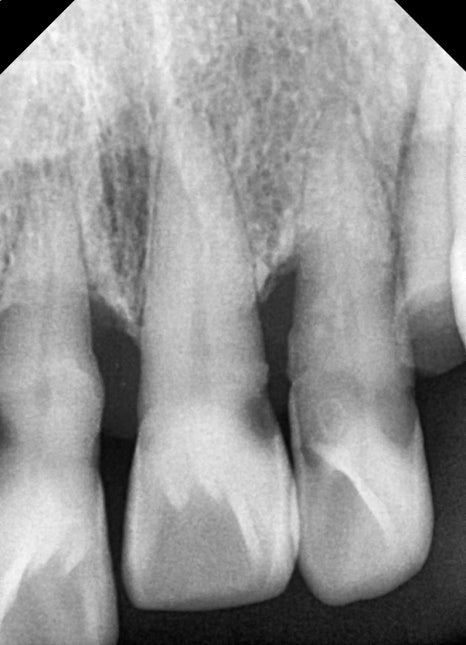

전치부 임플란트가 어려운 이유

앞니 임플란트는

어금니 임플란트보다 훨씬 까다로운 치료입니다.

그 이유는 다음과 같습니다.

잇몸 뼈가 얇음

잇몸 라인이 그대로 노출됨

발치와 동시에 진행된 임플란트 식립

이번 케이스에서는

손상된 앞니를 발치한 후

임플란트 식립이 동시에 진행되었습니다.

✔ 전치부 다수 임플란트 식립

✔ 골유도재생술(GBR) 진행

✔ 동종골 이식 병행

앞니는 뼈가 얇기 때문에

뼈이식

이 함께 진행되는 경우가 많습니다.

어금니와의 교합까지 고려한 치료

앞니 임플란트는 앞니만 맞춘다고 끝나는 치료가 아닙니다.

어금니 교합까지 함께 맞춰야

전체적인 균형이 유지됩니다.

이번 케이스에서도

어금니 교합 유지

전방유도 조정

전체 교합 균형 개선

이 함께 진행되었습니다.